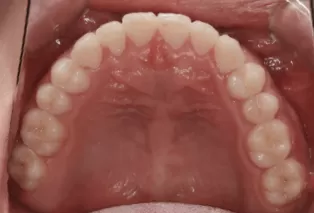

Male, 23 years old. Chief complaint: suffered from underbite for over 10 years.

Treatment outcome: straightened teeth, good occlusion, improved profile and smile.

Intraoral photos